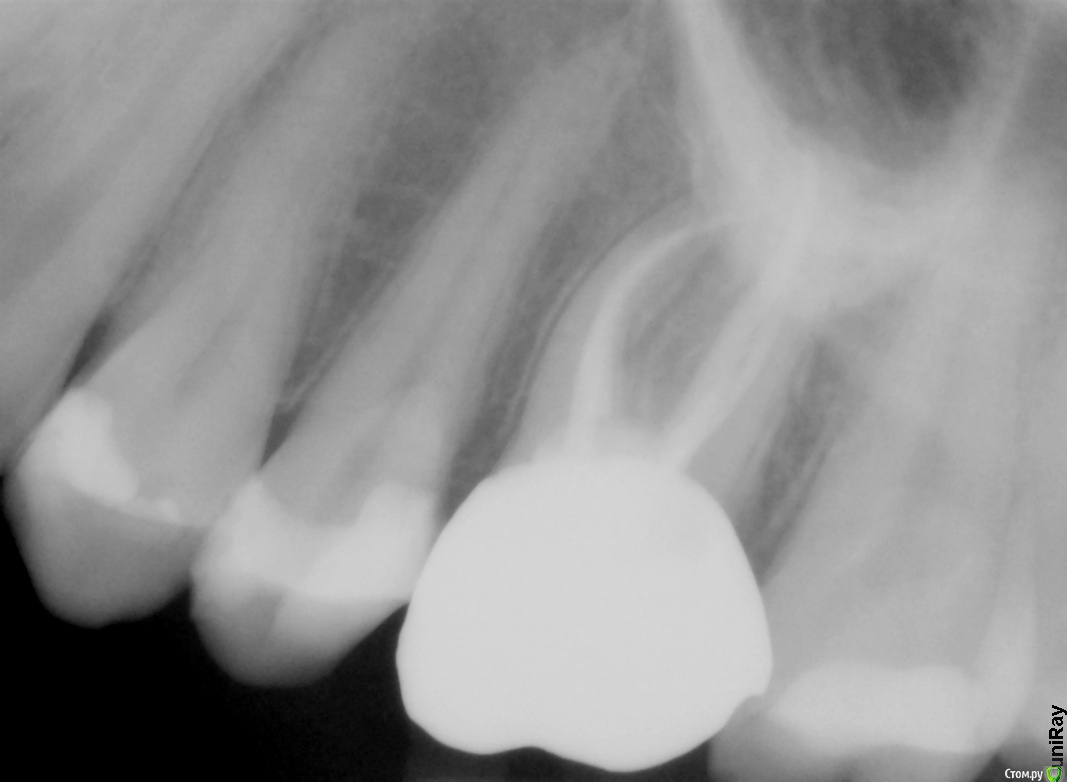

DaryaZel Опубликовано 11 мая, 2015 Автор Поделиться Опубликовано 11 мая, 2015 прикрепите все снимки лечения и можно будет говорить что то конкретноепо ситуации действительно обострился хронический пульпитБоюсь именно все снимки лечения мне достать не удасться. Пока прислали только один - последний. Ссылка на комментарий

DaryaZel Опубликовано 11 мая, 2015 Автор Поделиться Опубликовано 11 мая, 2015 Удалось получить из клиники только последний рентген - снят сразу после установки коронки на самый болящий зуб. Делали одновременно кариес и на двух соседний, левых зубах. Сейчас болит сосед коронки, больно при кусании. В клинике предположили, что он надломлен, и это вызвало воспаление нерва. Так как начали его снова полировать - а мне больно и даже после укола больно. Отправили меня к другому врачу на дополнительные тесты. По словам врачей, зуб мог надломиться из-за жевания чего-то трердого, но я почти этой областью не жевала, с самого начала проблем. Мог зуб треснуть от лечения кариеса? И чем это вообще грозит? Ссылка на комментарий